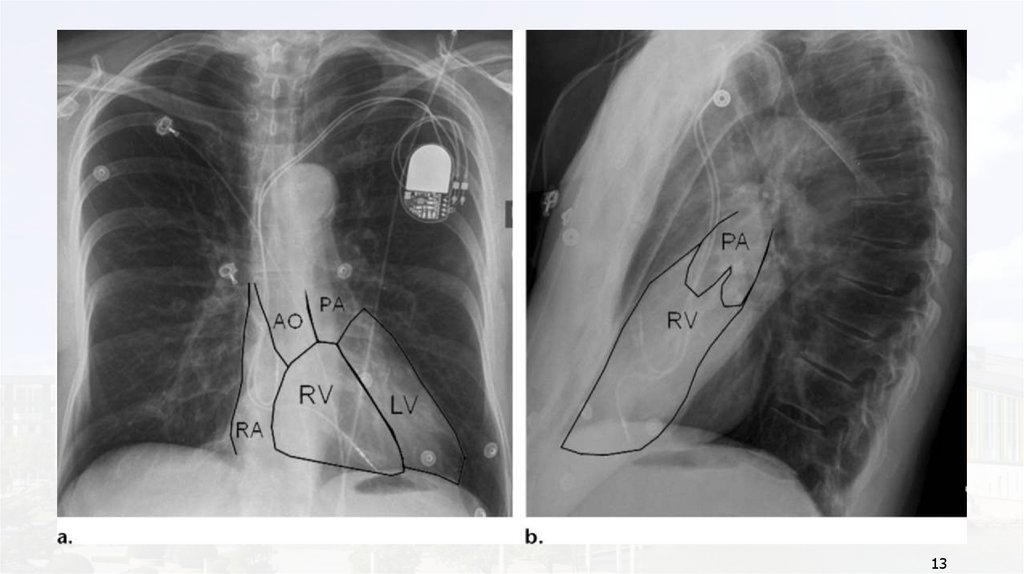

方而左

。是心

右室

心右

室心

在室

左不

心是

室并

右排

前排

上列

11